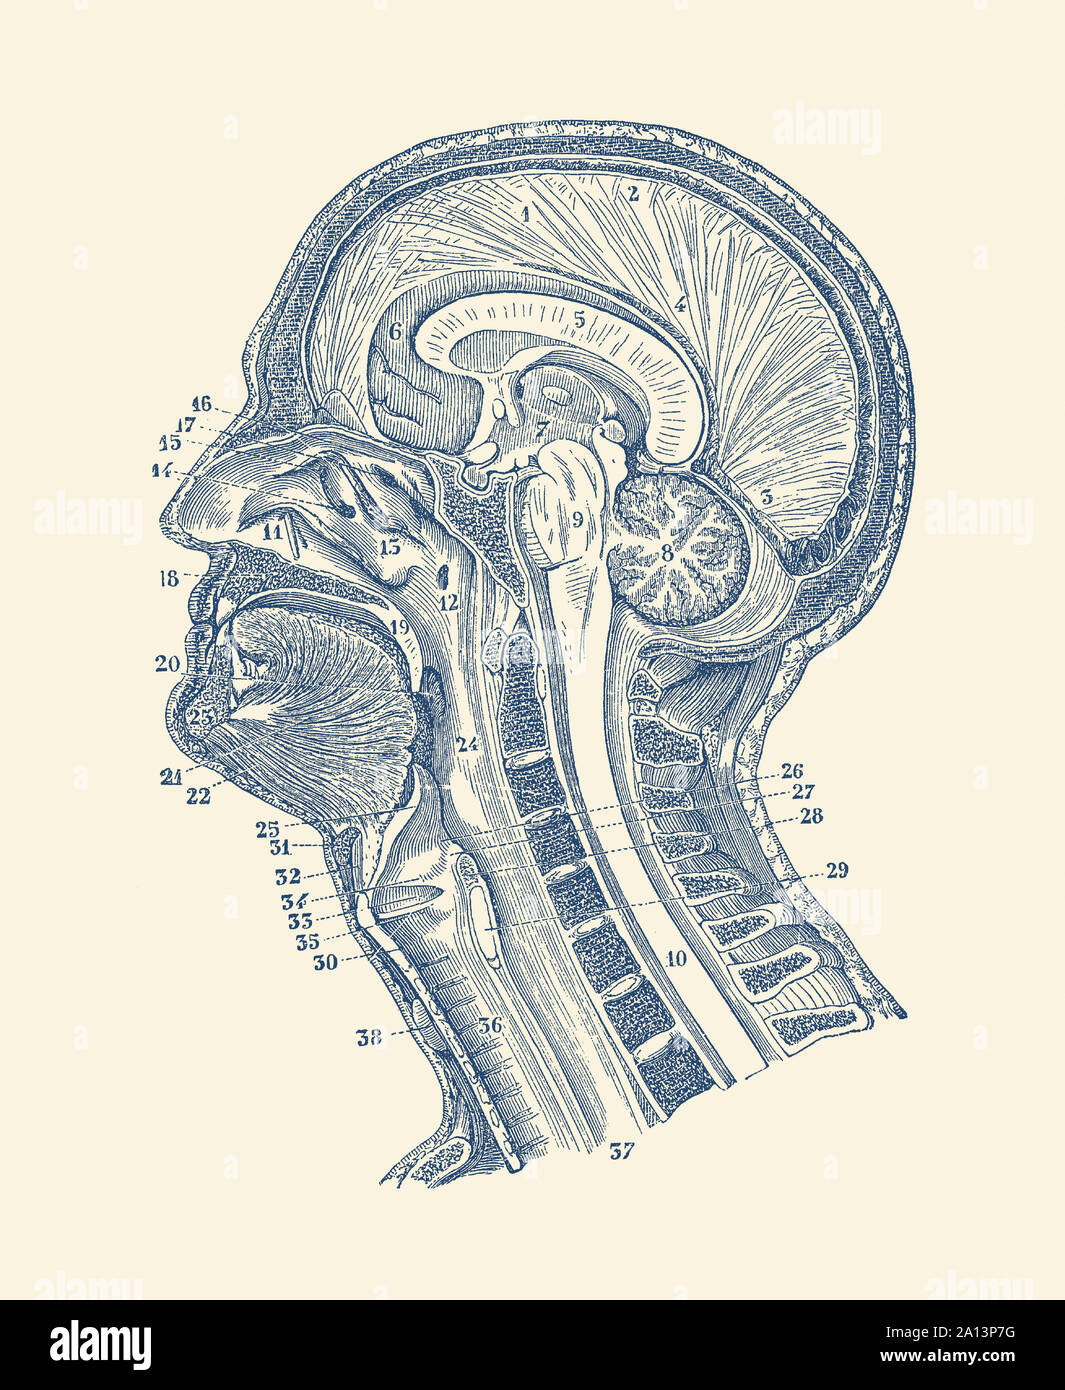

www.pxfuel.comAnatomía Vintage Imprimir Mostrando Un Diagrama De Estructuras En Y

www.pxfuel.comAnatomía Vintage Imprimir Mostrando Un Diagrama De Estructuras En Y

www.alamy.es24 Vintage Human Anatomy Diagram Posters Anatomical Systems - Etsy

www.alamy.es24 Vintage Human Anatomy Diagram Posters Anatomical Systems - Etsy